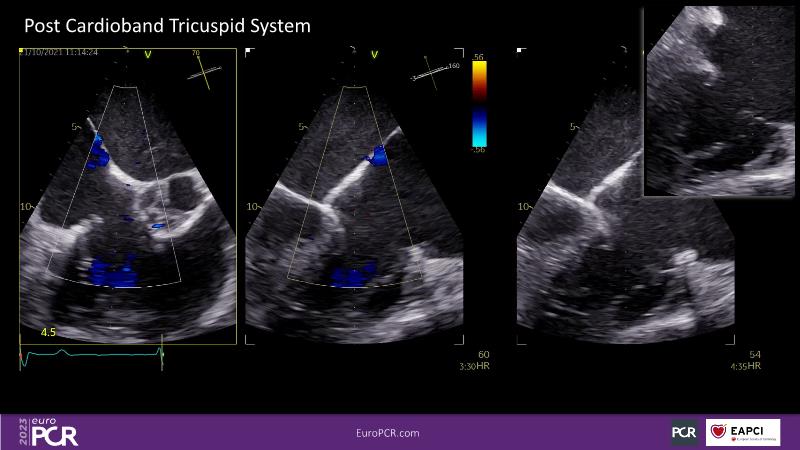

Watch this session to discuss exciting cases of tricuspid regurgitation, learn about the proposed new integrated classification for tricuspid regurgitation and enjoy a live presentation of the PASCAL Precision Repair System using a beating heart simulator, among others!

- To discuss the different tricuspid regurgitation phenotypes that can be treated with the PASCAL Precision repair system

- To participate in a case-based discussion using the PASCAL Precision repair system for the treatment of tricuspid regurgitation